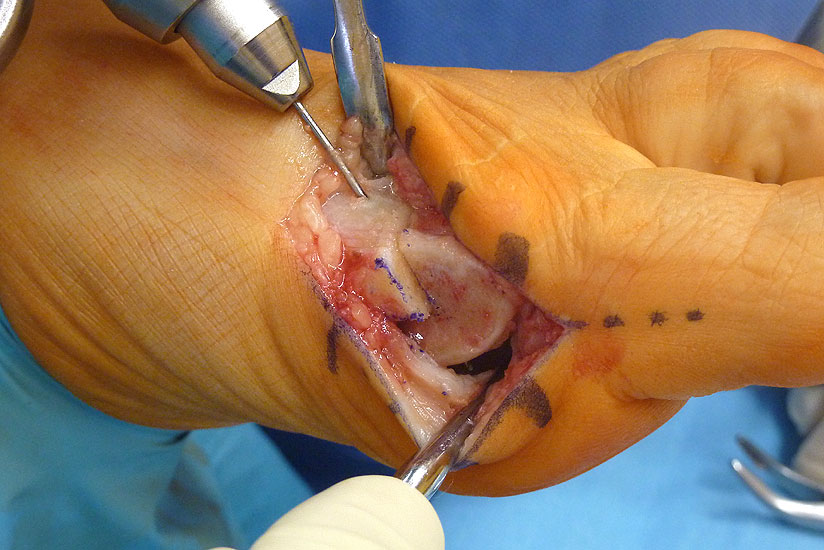

Operationstechnik

Abbildung 3

Abbildung 4

Abbildung 5

Abbildung 6

Abbildung 7

Abbildung 8